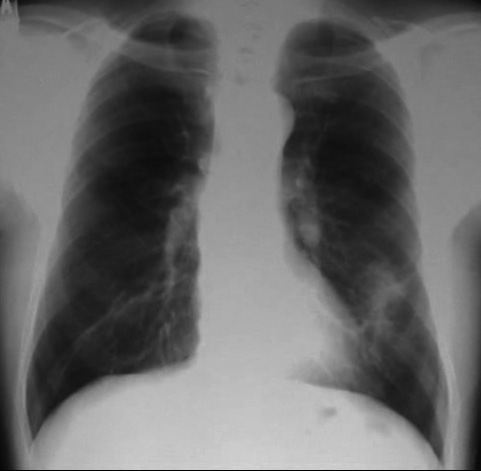

• X線検査では,通常,両肺の中・下部領域に多数の空洞化した転移性結節が認められる. 肺外への浸潤は極めて稀. 皮膚,中枢神経系,肝臓,腎臓などにも転移が見られる.

今月定期受診で1年ぶりにchest X-pを撮影. 両肺野に多発結節影が指摘されて受診となった.